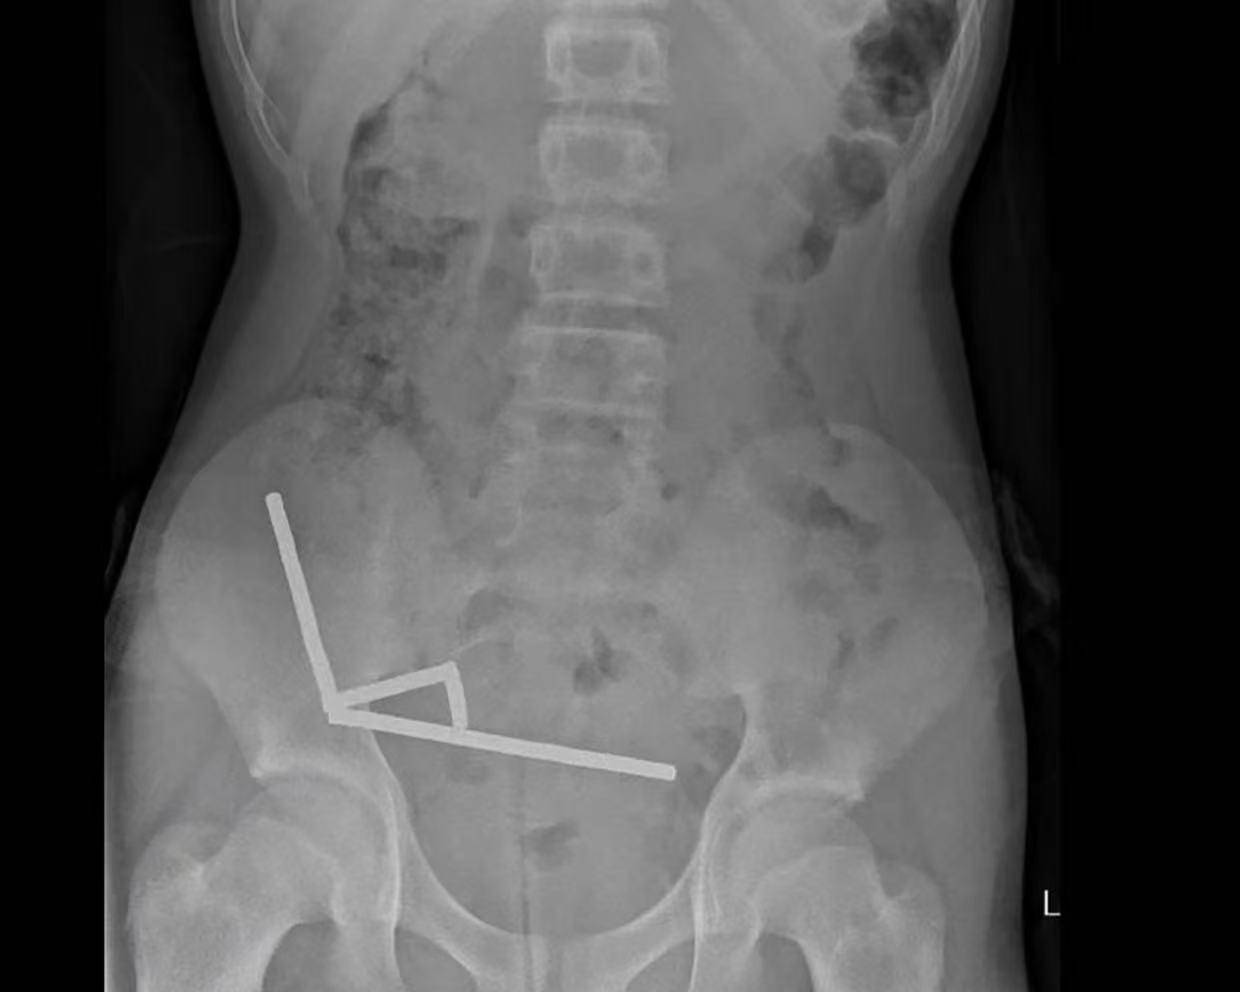

据悉,这名未透露姓名的少年在持续腹痛4天后被送往新西兰北岛的一家医院okex交易平台app下载链接。医生通过X光检查发现,这些磁铁在他的肠道内互相吸附,形成了四条链状结构。

▲X光显示okex交易平台app下载链接,磁铁在男孩体内紧密吸附成链状结构

据该院医生于周五在《新西兰医学杂志》上发表的报告称,外科医生取出了磁铁并切除了部分受损的肠组织okex交易平台app下载链接。磁铁的吸力导致男孩小肠及盲肠(属大肠的一部分)出现四处组织坏死。该男孩在住院8天后康复出院。

医生介绍,男孩大约一周前吞下了80至100颗大功率钕磁铁,每颗尺寸为5×2毫米okex交易平台app下载链接。报告称,这些磁铁通过一家跨境电商平台购买。